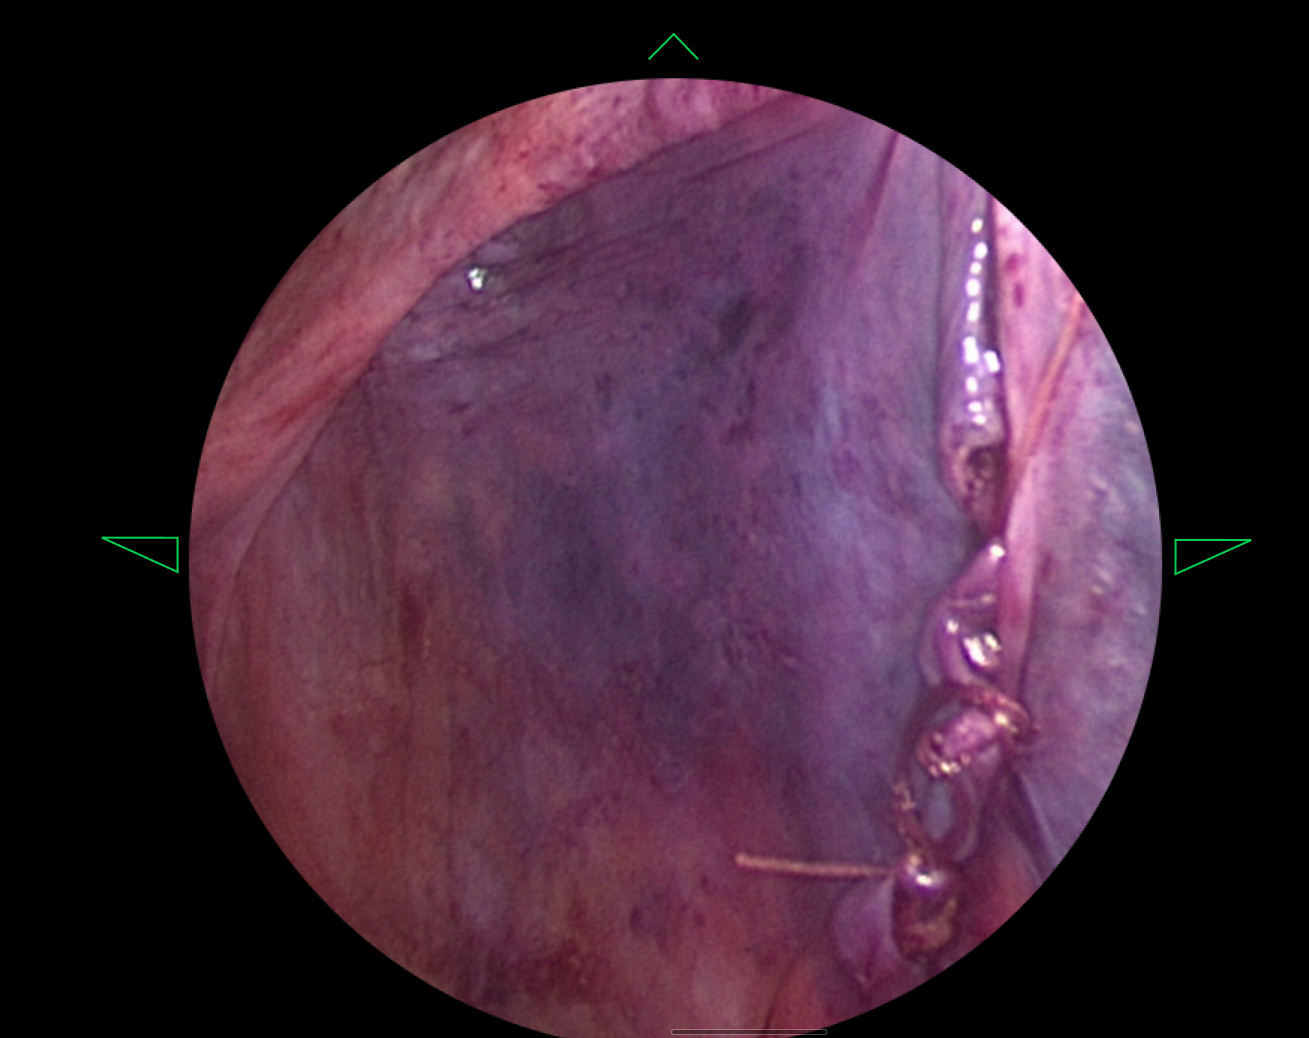

HUD Design: Surgery-Ready Interfaces

Operating rooms aren't like offices. I designed interfaces specifically for heads-up displays, considering lighting, distance, and the critical nature of surgical procedures.

- Created HUD displays that surgeons could actually use